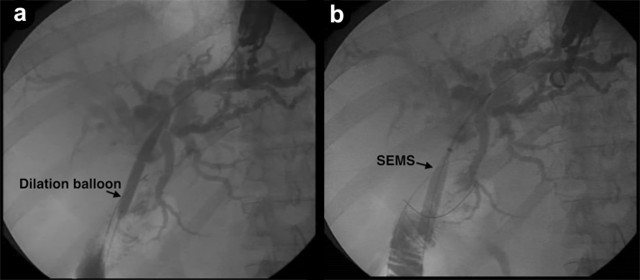

Contrast was injected to demonstrate the jejunal position of the guidewire, and showing the length of the stenosis (Figure 2). A 6 mm guidewire balloon dilation was performed, followed by the placement of a partially covered self-expandable metallic stent (10x60 mm, Wallflex, Boston Scientific, Natick, MA, USA), across the anastomosis (Figure 3). Adequate contrast drainage was observed (Figure 4).

|

Figure 3. a. Radiological image demonstrating the dilation balloon. b. Self-expandable metal stent partially opened. |